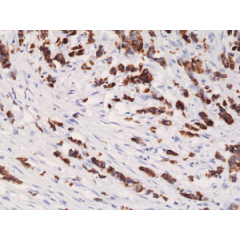

anti-Cytokeratin-20 (human), Rabbit Monoclonal (RM283)

anti-Cytokeratin-20 (human), Rabbit Monoclonal (RM283)

REV-31-1166-00 REV-31-1166-00-R100 100 µl CHF 468.00